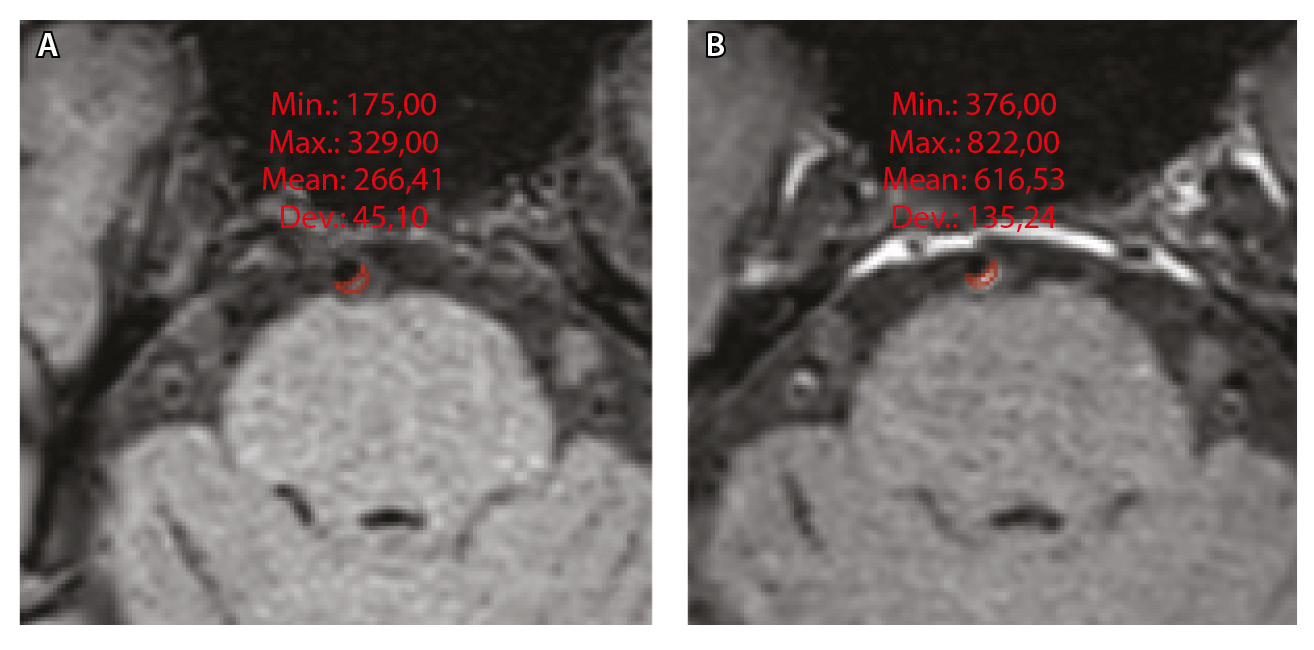

Для количественной оценки степени накопления контрастного вещества в области интереса (АСБ, неизмененная сосудистая стенка, воронка гипофиза) рассчитывали WEI по формуле:

где WEI (wall enhancement index) – индекс усиления контрастности стенки (сосудов), SIwallprecontrast – интенсивность сигнала (Signal Intensity, SI) сосудистой стенки (wall) в зоне интереса на преконтрастных (precontrast) изображениях, SIwallpostcontrast – интенсивность сосудистой стенки в зоне интереса на постконтрастных (postcontrast) изображениях; SIbrainprecontrast – интенсивность неизмененного белого вещества мозга (brain) на доконтрастных изображениях; SIbrainpostcontrast – интенсивность неизмененного белого вещества мозга на постконтрастных изображениях. Пример измерения интенсивности сигнала от АСБ для расчета WEI приведен на рисунке 1.

Рис. 1. Пример измерения интенсивности эхо-сигнала от атеросклеротической бляшки базилярной артерии для расчета индекса усиления контрастности стенки сосуда (WEI). В месте максимального стеноза артерии на одном срезе отмечали область интереса (ROI) и регистрировали среднее значение интенсивности сигнала от сосудистой стенки (SIwall). ROI были сопоставлены по размеру и местоположению в наборе данных T1-TSE-db-FS до (А) и после (Б) контрастного усиления; макс. – максимум, мин. – минимум, откл. – отклонение, средн. – среднее